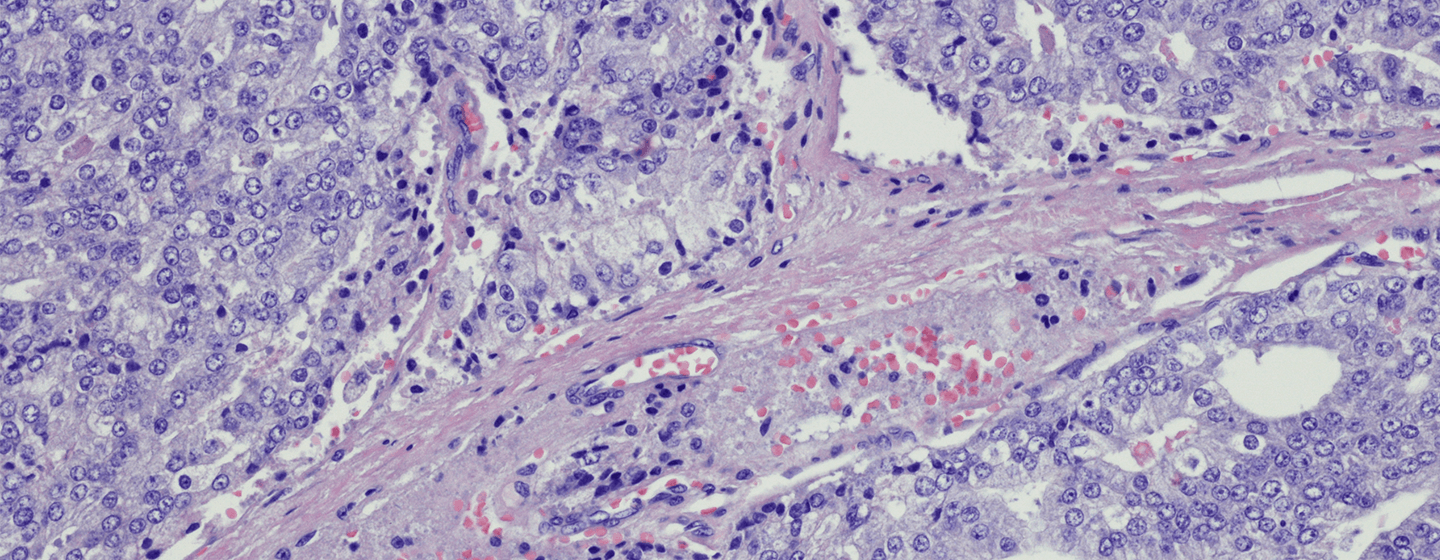

A study by QIMR Berghofer Medical Research Institute has for the first time identified that bowel cancer has five distinct subtypes that are closely related to a patient’s age.

Associate Professor Whitehall said the study found bowel cancer could be classified according to methylation of the genes – or simply put, how the genes turned on or off.

“DNA methylation is a way a cell can turn its own genes on or off, but in cancer this process gets hijacked and it turns on genes that favour growth and turns off genes that are meant to suppress it.